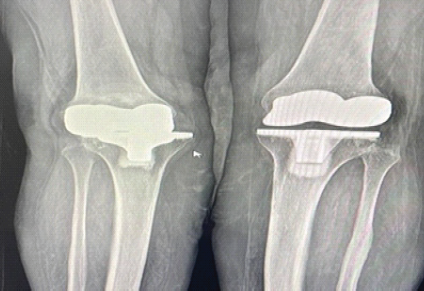

A 63-year-old female presented with pain, swelling, and reduced flexion in the right knee following a fall 2 months earlier. She also reported a 3-year history of recurrent instability, sudden locking, and restricted motion, which she occasionally relieved by self-manipulation. She had undergone bilateral TKR (left knee 15 years ago and right knee 12 years ago) using the Stryker Duracon system. At a local hospital, X-ray imaging, as shown in Figs. 1 and 2, revealed tibial component loosening, polyethylene liner dissociation, and marked osteolysis. Laboratory parameters (complete blood count, erythrocyte sedimentation rate, and C-reactive protein) were normal, excluding infection.

Figure 1: There is osteolysis, dislocation, and implant loosening in the right knee, whereas the left knee appears normal in anteroposterior X-ray.